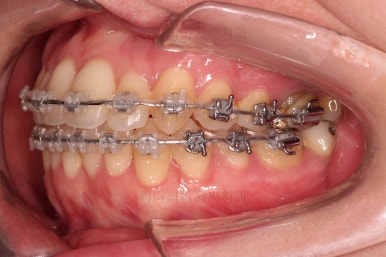

초진 시, 입안의 모습입니다.

좌측 송곳니가 덧니처럼 튀어나가 있고, 송곳니 옆의 작은 억므니가 안으로 쏙 들어가서 덧니 느낌이 더 강조되어 보이네요.

위아래 앞니가 긴밀하게 겹침이 없는 약간의 개방교합(오픈바이트, Openbite) 경향이 보입니다.

웃거나 말할 때 드러나는 치열이 삐뚤어서 심미적으로 좋지 못하고요.